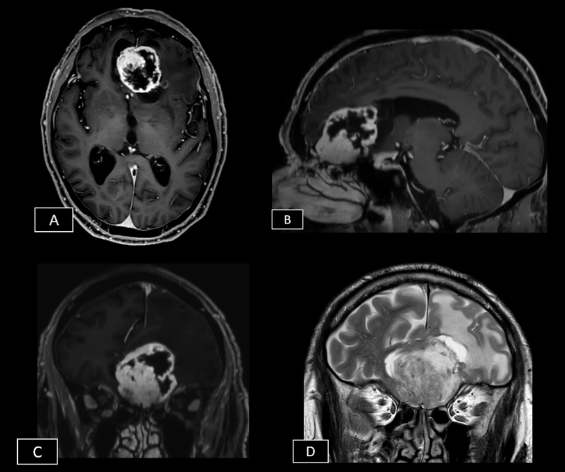

Caso del mes Noviembre 2025

Autor/Autores

Sara Septién Rivera; Josep Castell Aulet; Mildred Viveros Castaño. Área de Neurorradiología, Hospital Universitario de Bellvitge, Barcelona, España Mail: sseptien@bellvitgehospital.cat